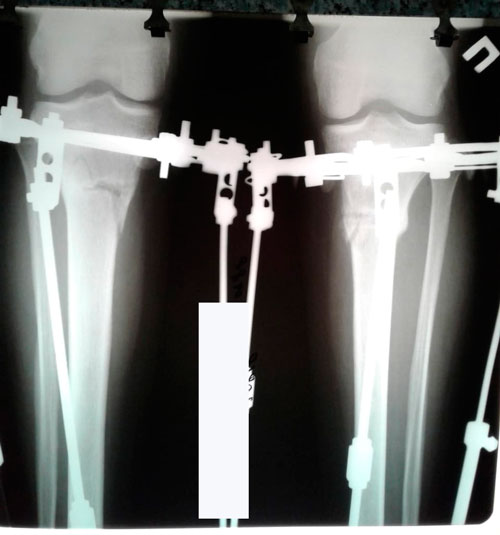

Дата операции 14.05.2018г.

Дата снятия аппаратов 09.08.2018г.

Срок лечения 85 дней.